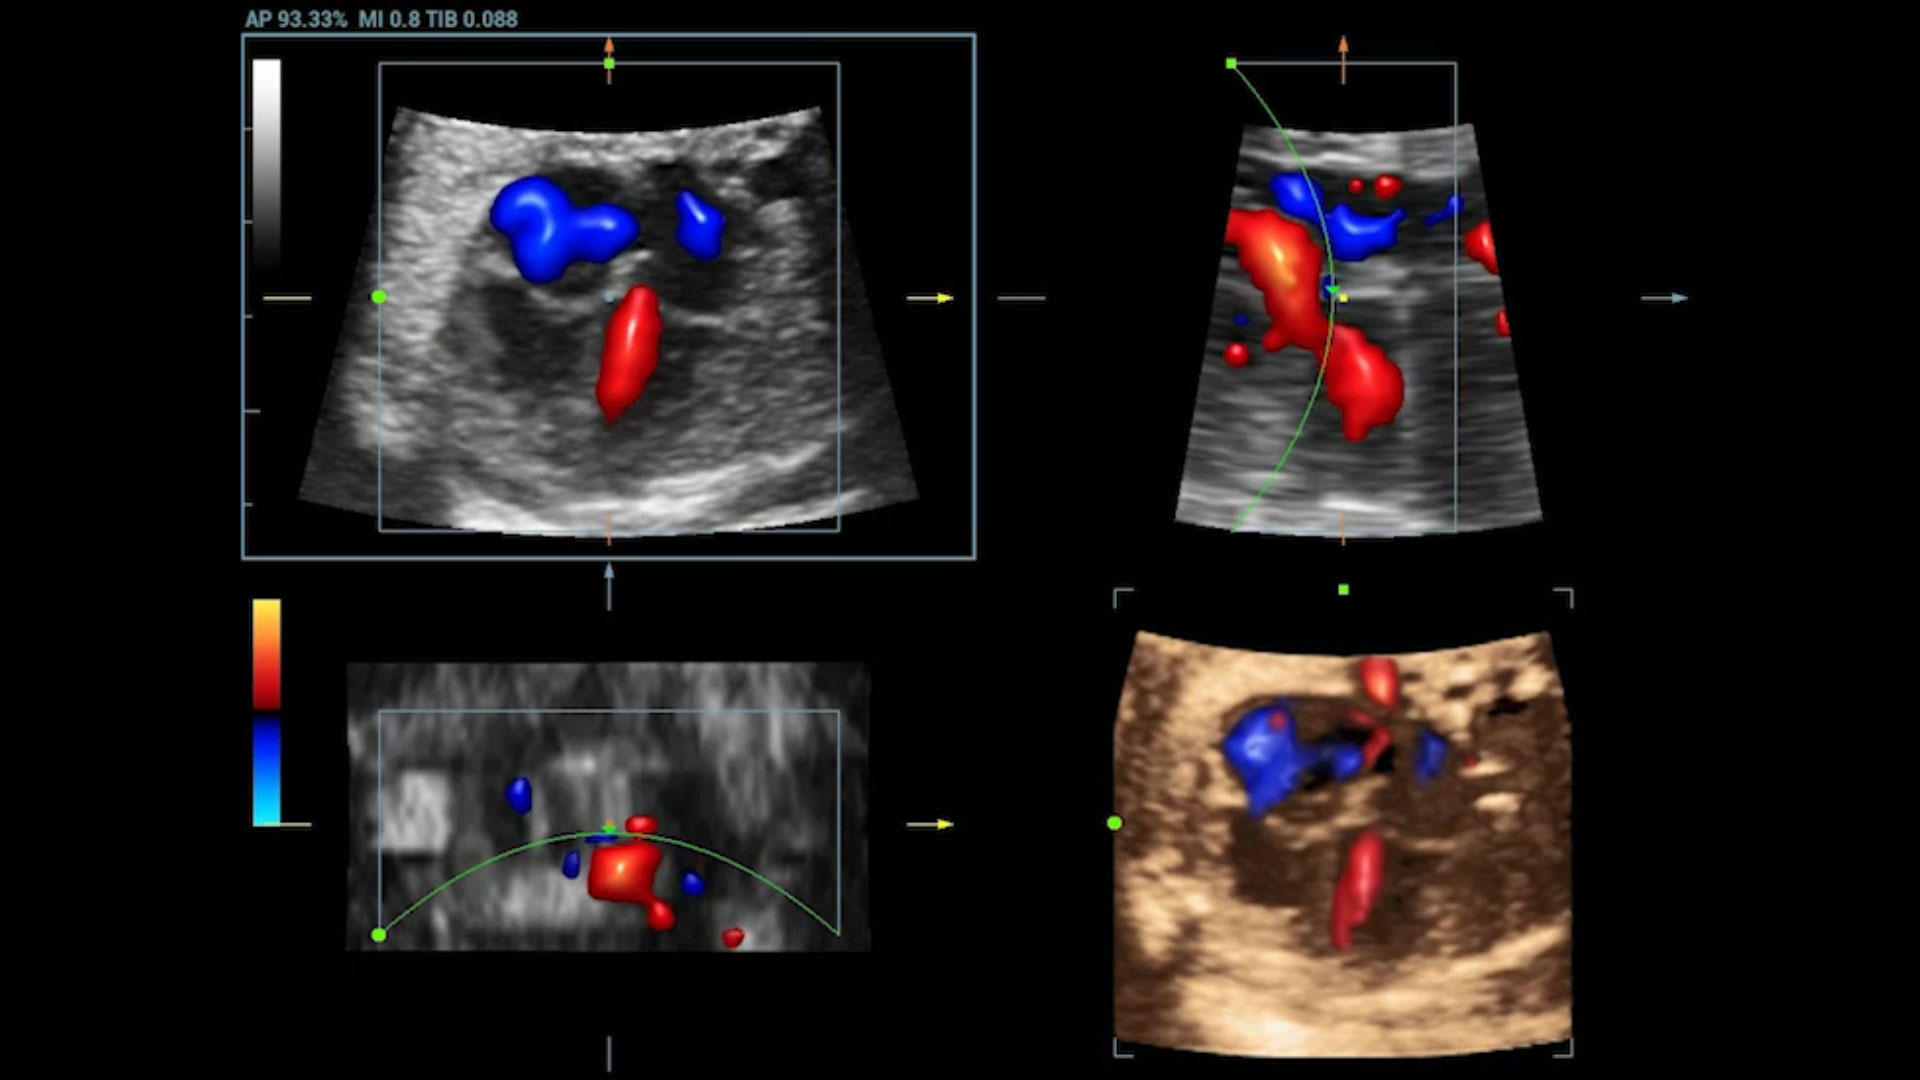

UMA (angiografia ultramicroscĆ³pica)

A tecnologia inovadora elimina as limita??es das tradicionais imagens com Doppler. Com resolu??o espacial e sensibilidade de fluxo ultra-altas, permite a detec??o de perfus?es de fluxos muito sutis e lentos, ampliando assim a aplica??o clĆnica da avalia??o qualitativa e quantitativa do ultrassom no cĆ©rebro fetal, rins, placentas, endomĆ©trios, ovĆ”rios etc.

UMA ā Fluxo renal do feto

UMA 3D ā Fluxo intracraniano do feto

UMA ā Fluxo uterino e endometrial

UMA 3D ā Fluxo sanguĆneo perifolicular